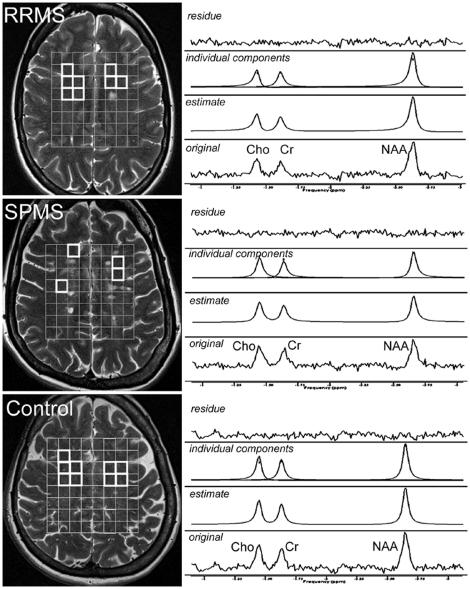

37 patients with clinical definite MS (27 with RRMS, 10 with SPMS) and 8 controls were included. We used 2D (1)H-MR-chemical shift imaging (TR = 1500ms, TE = 135ms, nominal resolution 1ccm) operating at 3Tesla to assess the metabolic pattern in the fronto-parietal NAWM. Ratios of NAA to creatine (Cr) and choline (Cho) and absolute concentrations of the metabolites in the NAWM were measured in each voxel matching exclusively white matter on the anatomical T2 weighted MR images.

No significant difference of absolute concentrations for NAA, Cr and Cho or metabolite ratios were found between RRMS and controls. In SPMS, the NAA/Cr ratio and absolute concentrations for NAA and Cr were significantly reduced compared to RRMS and to controls.

CONCLUSIONS

In our study SPMS patients, but not RRMS patients were characterized by low NAA levels. Reduced NAA-levels in the NAWM of patients with MS is a feature of progression.